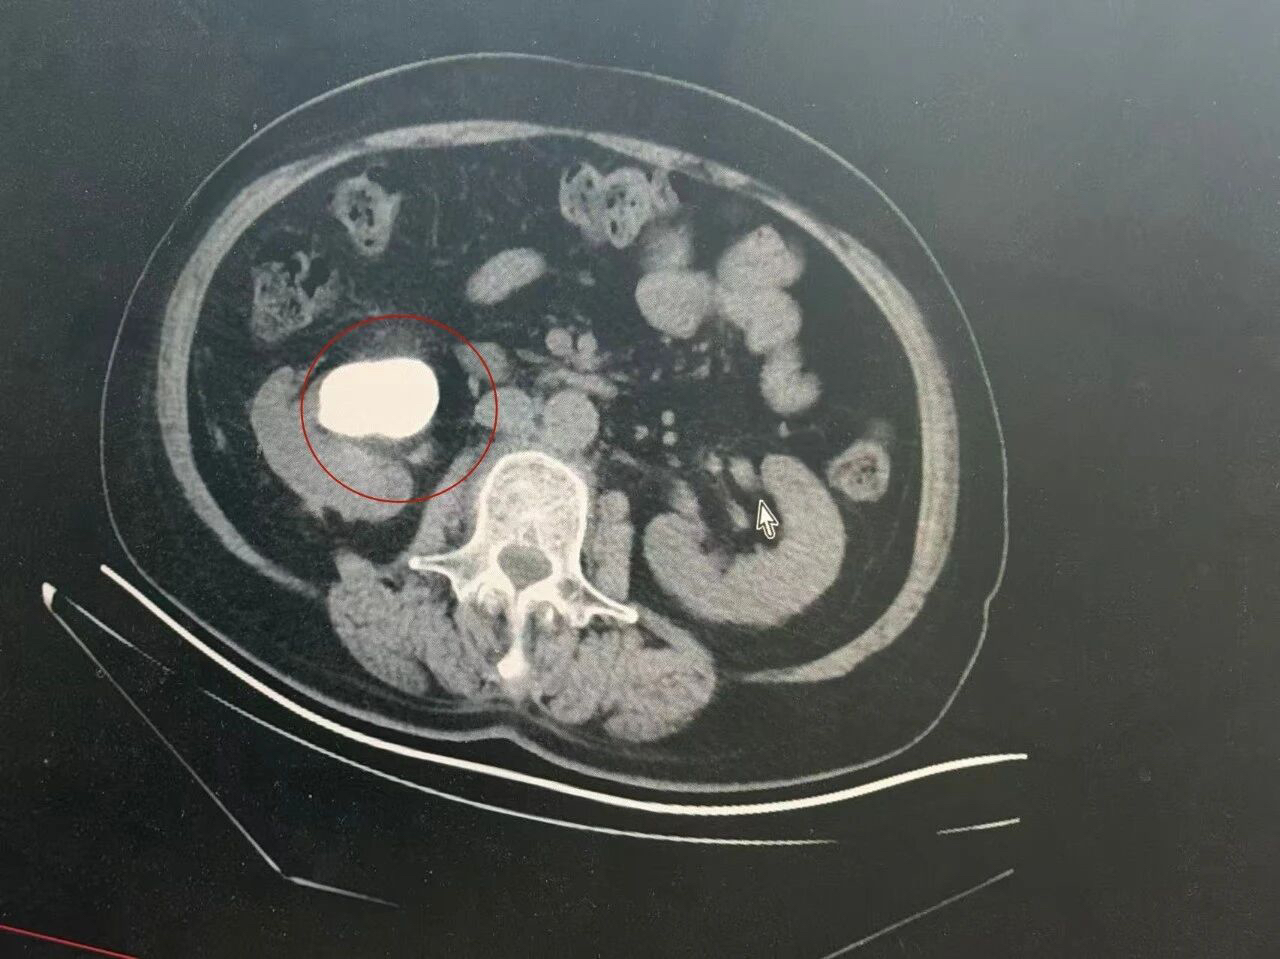

占据肾脏的巨大结石

近年来,58岁的姚女士常常觉得右侧腰部隐隐作痛,她以为是劳累所致,便没有太在意。直到近月来,她感觉疼痛剧烈,伴有尿频、尿急,于是便找到江都人民医院泌尿外科主任王荣博士看诊。让她惊讶的是,B超检查发现她的右肾已被巨大的结石所占据。CT扫描下,这个巨大的结石呈铸型结构,形似“鹿角”,竟然完全“复制”了肾盂形态,宛如肾脏内部的“倒模”。